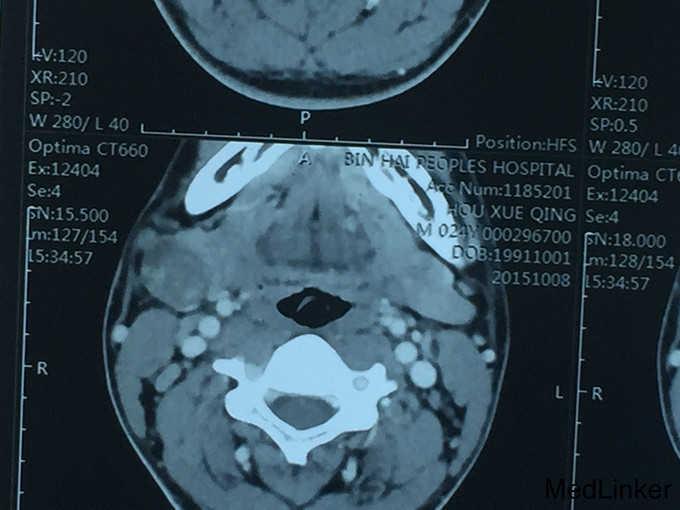

查体:右颌下区可扪及肿物大小约4*3*3cm,质地中等,活动,轻度压痛,和颌下腺相连,颌下腺导管口无红肿,分泌畅。 复查:CT:颌下腺多行性腺瘤可能

诊断:右颌下腺多形性腺瘤可能 治疗:全麻下右颌下腺及肿物切除,术中病理:右颌下腺多形性腺瘤